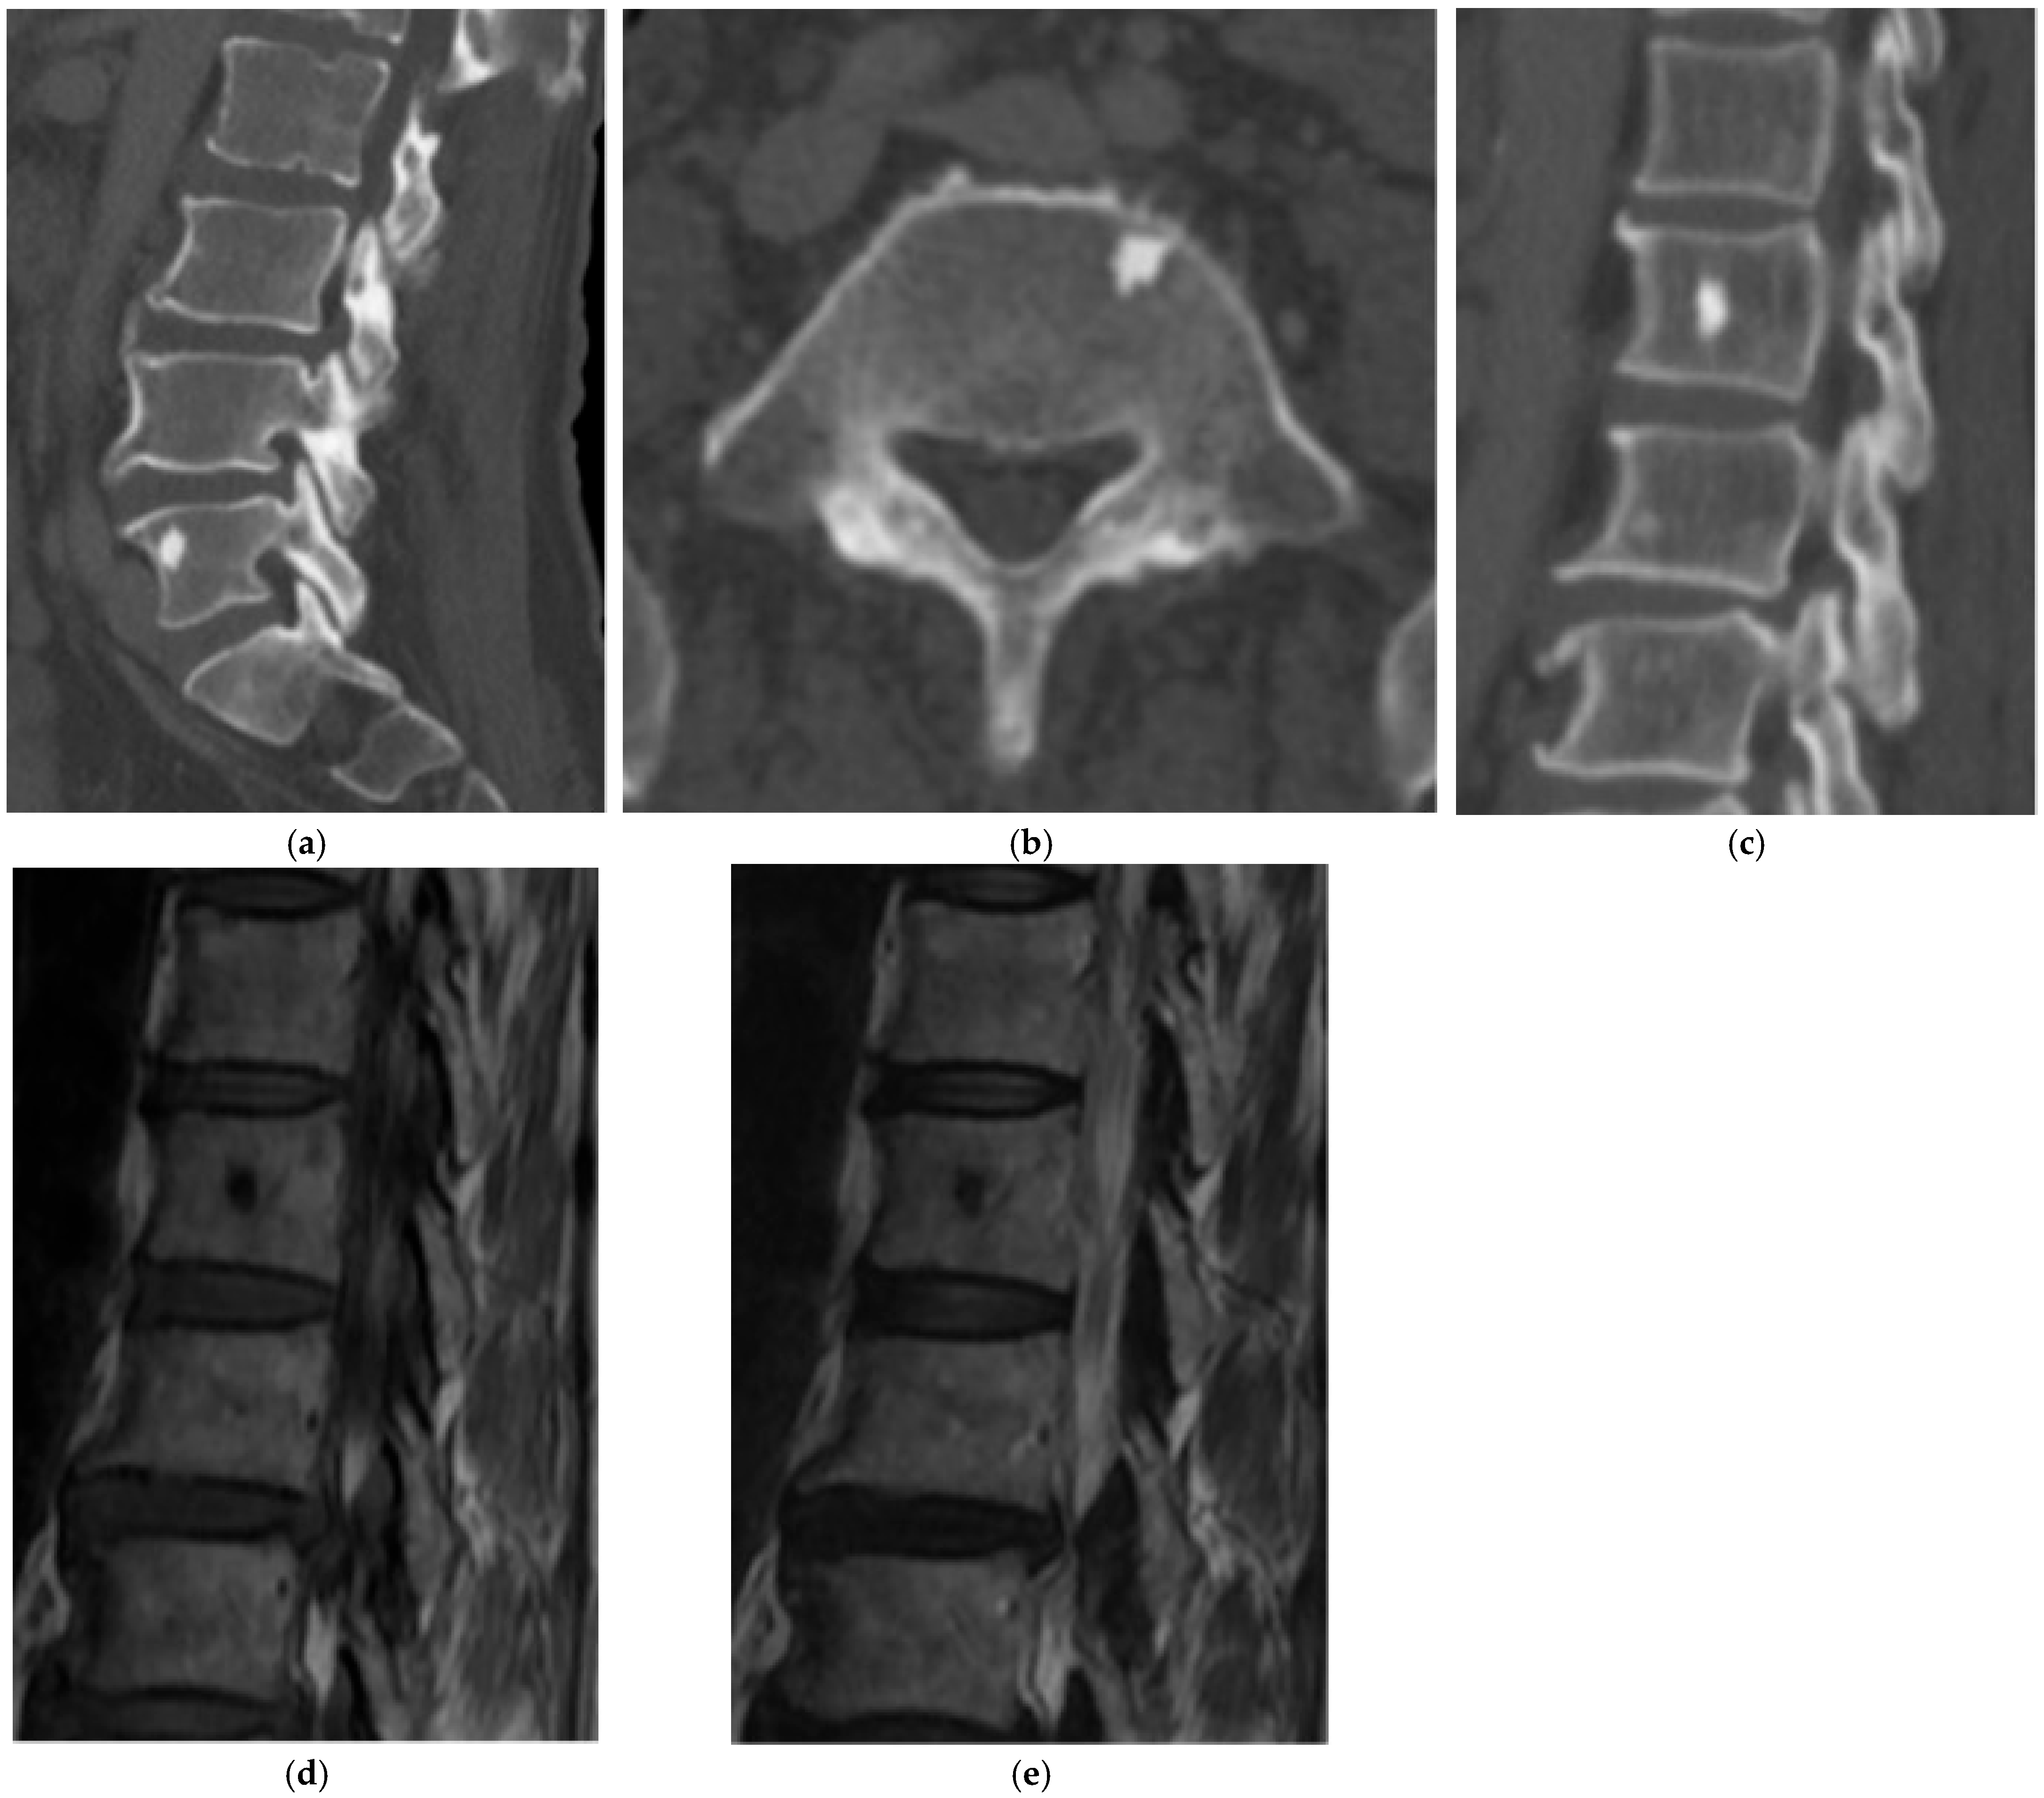

2.1.2. Osteoid Osteoma